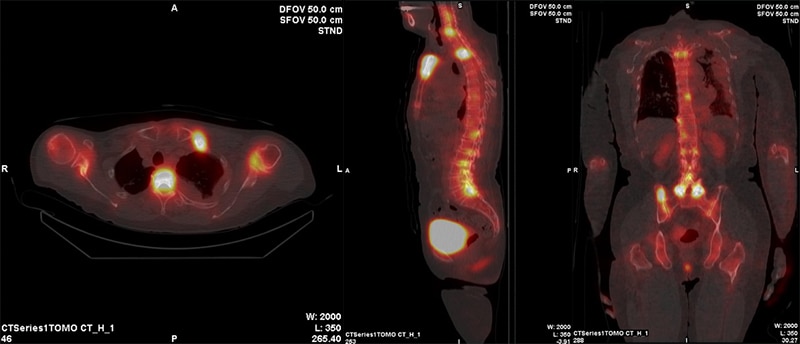

心筋血流シンチグラフィでは吸収補正のためにCT撮影を行っています。CTの吸収補正により、下壁部分の減弱の影響が改善された画像を出力することが出来ます。また、解析用ワークステーションXelerisで吸収補正あり・なしの比較画像を作成し、読影しやすい画像出力に努めています。

ピロリン酸シンチグラフィ検査では通常SPOT像における定量値、定性画像の評価により心アミロイドーシスの鑑別を行いますが、それに加えてSPECT/CTのFusion画像を作成することによって心筋へのピロリン酸の集積をより分かりやすく表示することが可能です。

テクネチウム心筋血流シンチグラフィ

上段2つ:吸収補正なしNC、下段2つ:吸収補正あり AC

ピロリン酸シンチグラフィ CT画像とのFusion